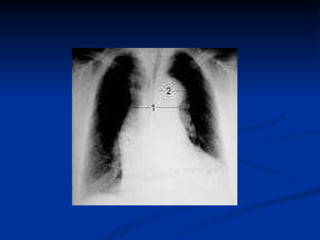

CHEST X-RAY 1. widened mediastinum, (sen: 44-80%) 2. Calcium sign -Displaced intimal calcification (>10mm) from outer aortic wall– useful in older patients 3.pleural effusion (involvement of descending aorta) 4.Normal in 18% A Normal CXR Should Not Deter Further Evaluatio n.

CHEST X-RAY 1.widened mediastinum, (sen: 44-80%) 2. Calcium sign -Displaced intimal calcification (>10mm) from outer aortic wall– useful in older patients 3.pleural effusion (involvement of descending aorta) 4.Normal in 18% A Normal CXR Should Not Deter Further Evaluatio n.